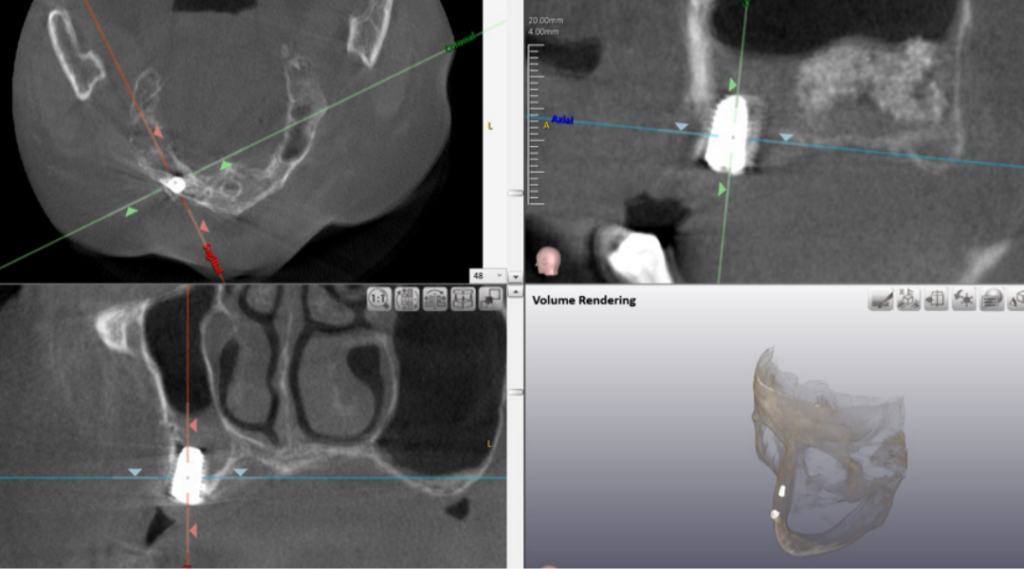

➤ 無料カウンセリング詳細精密検査・診断

歯科用CT等を用い、骨の量・質、神経や血管の位置、噛み合わせを多角的に確認。安全性を最優先した精密なシミュレーションを行います。